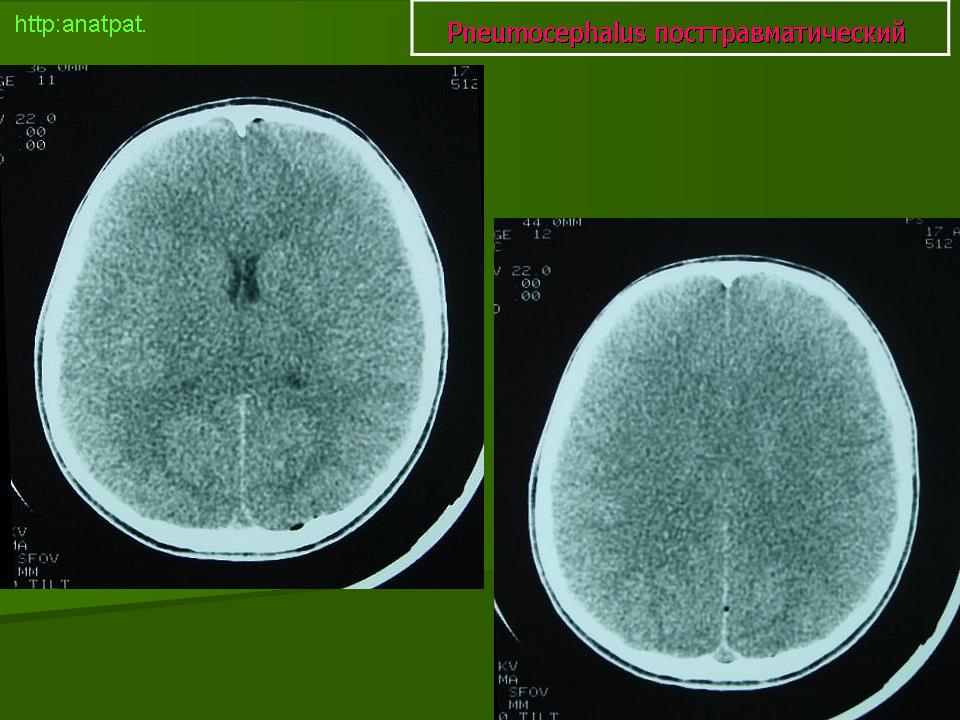

Напряженная пневмоцефалия возникает чаще всего после удаления субдуральной гематомы, но также описаны случаи в результате операций на основании черепа, пазухах носа, задней черепной ямке в положении сидя или при травме головы.

Напряженная пневмоцефалия характеризуется повышенным давлением воздуха в субдуральном пространсте. Повышенное давление воздуха является следствием клапана механизма, при котором воздух входит в субдуральное пространство через дефект в кости черепа, но выход воздуха заблокирован. Напряженная пневмоцефалия приводит к масс-эффекту и сдавлению лобных долей. Присутствие воздуха между лобными долями означает, что давление субдурального воздуха превышало поверхностное натяжение спинномозговой жидкости между лобными долями (Michel S.J.: Симптом горы Фудзи. Радиология, 2004, 232: 449-450).

Правильный диагноз напряженной пневмоцефалии ставиться при тщательной корреляции клинических и КТ признаков.